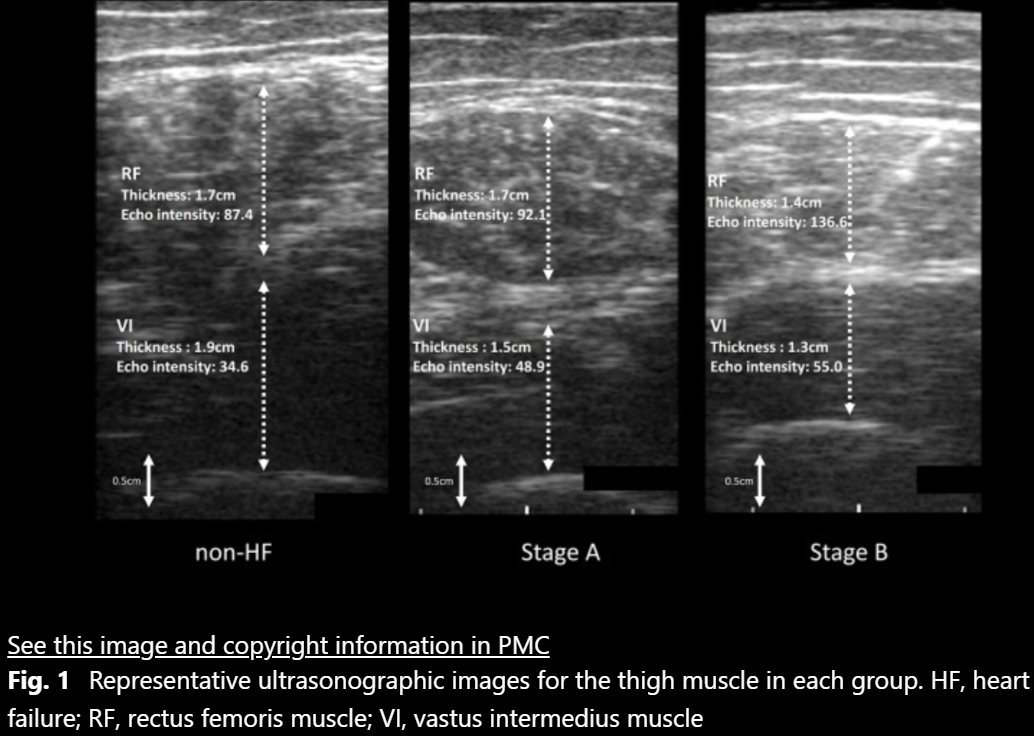

Association between heart failure in asymptomatic stages and skeletal muscle function assessed by ultrasonography in community-dwelling older adults.

Toshimi Satoh, Yosuke Kimura, Tomohiro Kakehi et al.  |  BMC Geriatrics 24: 871  |  2024年10月

Representative ultrasonographic images for the thigh muscle — BMC Geriatrics 2024

地域在住高齢者における無症候性心不全の罹患と骨格筋機能の関係-超音波画像を用いた調査-

第8回日本栄養・嚥下理学療法研究会 セレクション演題  |  2023年3月